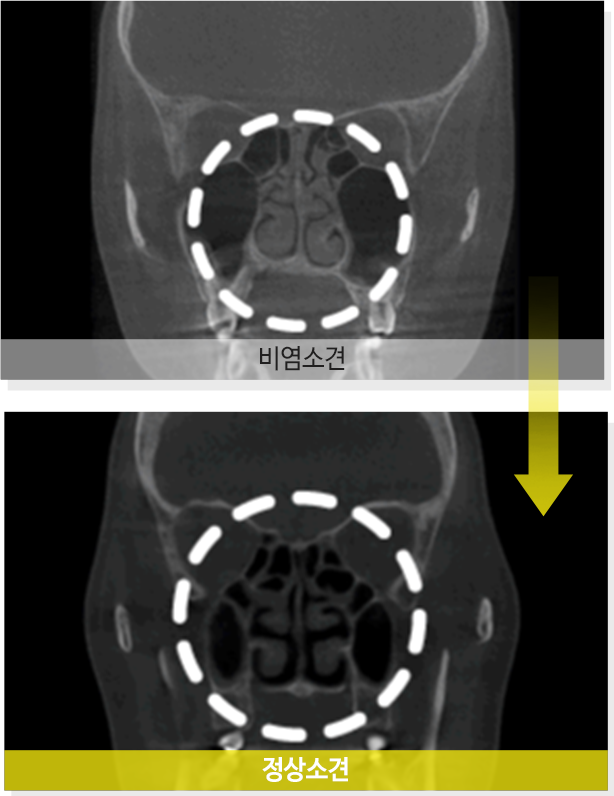

알레르기성 비염이라면 재발할 우려가 있지만

비알레르기성 비염의 경우에는 재발할 확률이 적습니다.